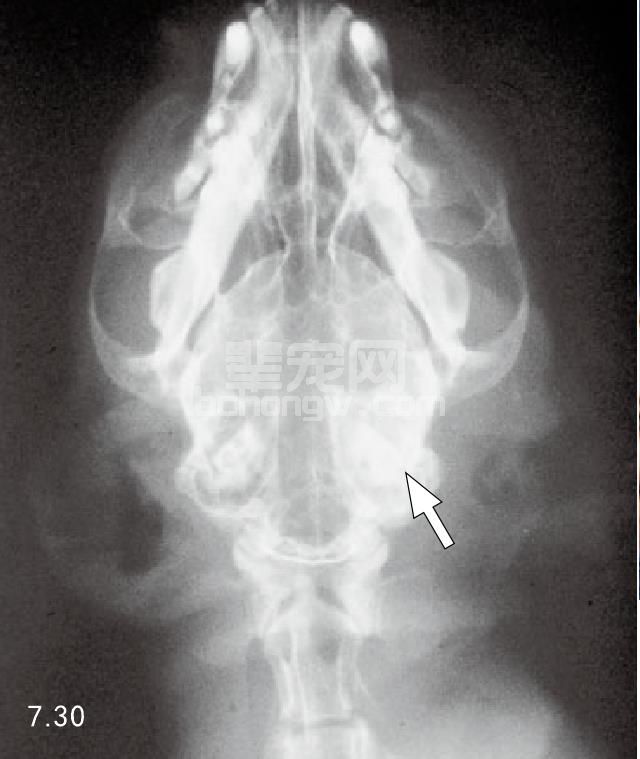

病因学 在犬、猫中耳炎的扩散损害了内耳是常见的外周性前庭病病因(图7.30)。

图7.30 猫中耳炎时的外周性前庭病症状,因慢性感染,左侧鼓室明显硬化(箭头所指)。